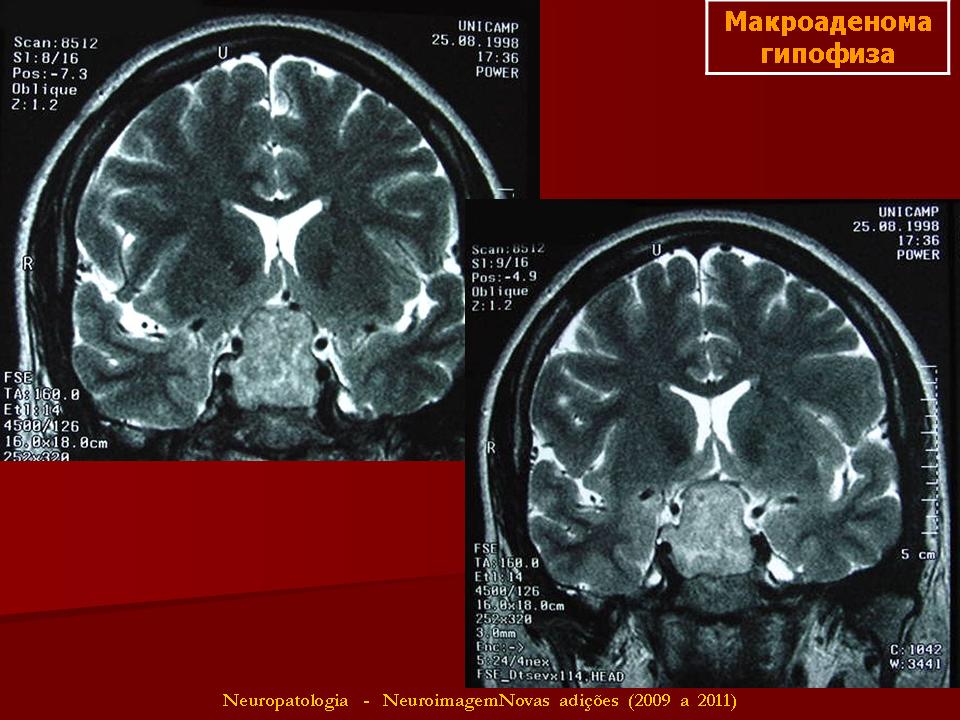

Гормонально-неактивные аденомы - аденомы, патогенез нарушений при которых заключается в увеличении объема опухоли, расположенной в передней доле гипофиза и в воздействии этого объема на гормонально-активные клетки гипофиза, что приводит к их нарастающей атрофии. Наряду с этим опухоль воздействует на анатомические образования мозга - зрительные нервы, хиазму, черепные нервы, гипоталамус, внутренние сонные артерии. К этим опухолям относятся хромофобная аденома и онкоцитома.

Аденомы гипофиза во всех наблюдениях имеют эндоселлярное расположение. Вместе с тем у многих больных они могут находиться еще за пределами турецкого седла. Если опухоль распространяется над турецким седлом, то в этом случае говорят о супраселлярном росте, за спинку седла - о ретроселлярном, в стороны от турецкого седла - о параселлярном, а кпереди от турецкого седла - об антеселлярном росте опухоли. Как правило, имеется комбинация нескольких направлений роста аденомы гипофиза.

Чаще всего (10-30% от всех внутричерепных новообразований) в этой области встречаются опухоли гипофиза (аденогипофиза), рост которых сопровождается вытеснением опухолью неизмененной железистой ткани гипофиза, гормональной активностью новообразования, деструкцией стенок турецкого седла, компрессией прилежащих анатомических структур головного мозга и отходящих от него черепных нервов. 80% опухолей гипофиза доброкачественные, но их постепенный рост в пределах, ограниченных турецким седлом и расположенным над ним областях, способен привести к серьезным эндокринным и неврологическим осложнениям. Разнообразие эндокринной патологии и сложность оценки клинических и морфологических изменений требует тщательного обследования в специализированных отделениях.